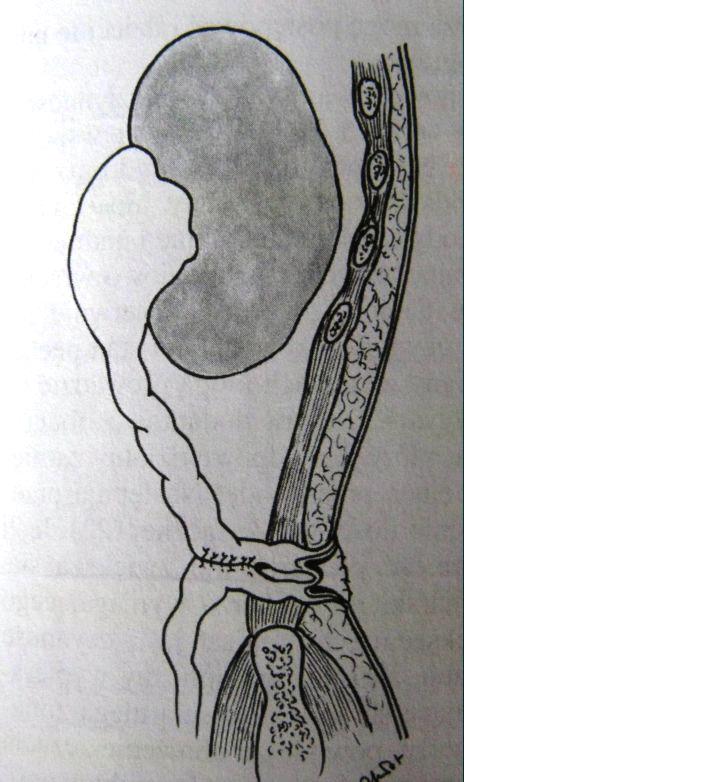

Poniższy rysunek przedstawia schemat plastyki połączenia miedniczkowo-moczowodowego:

Na rysunku widnieje schemat przetoki moczowodowo-skórnej: